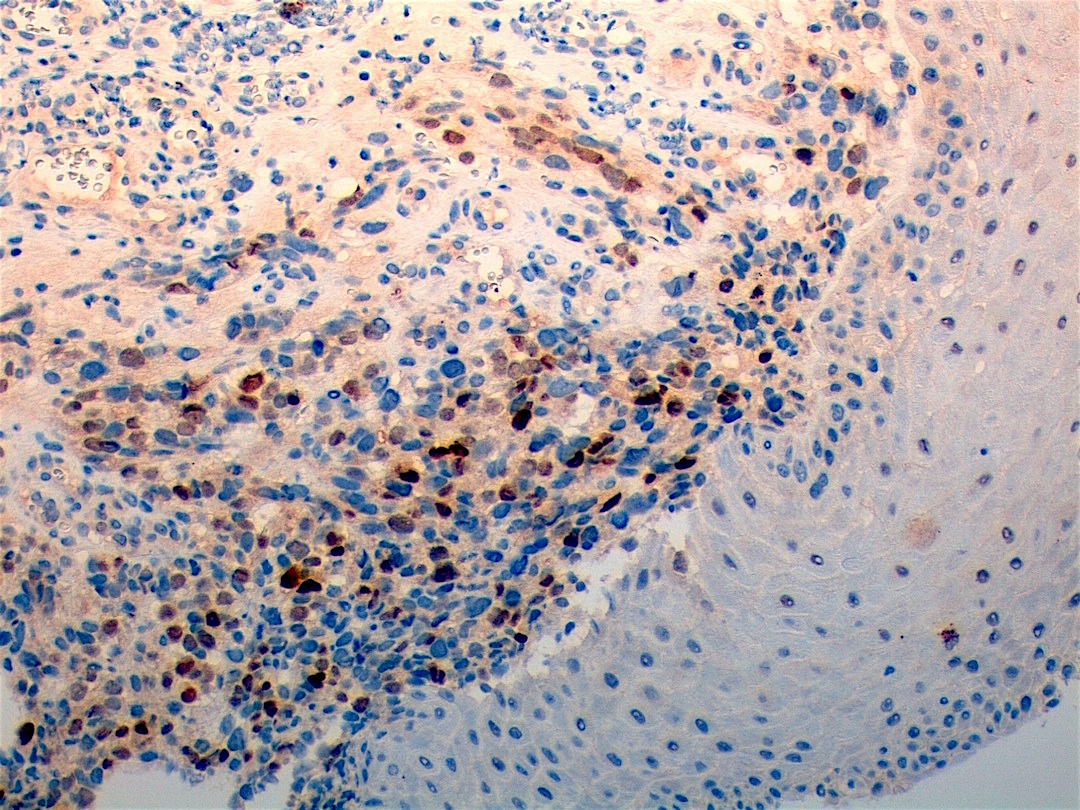

Microscopic (histologic) images

Contributed by Erdener Özer, M.D., Ph.D. and Mark R. Wick, M.D.

Contributed by Carolina Martinez Ciarpaglini, M.D., Ph.D. (Case #276) - tonsillar mass

AFIP images - anaplastic rhabdomyosarcoma

AFIP images - botryoid variant

Positive stains

- Desmin, MyoD1 or myogenin are critical to document (Pathol Oncol Res 2008;14:233)

- Without myogenic differentiation (MyoD1 or myogenin), it is very difficult to diagnose embryonal rhabdomyosarcoma

- These stains will be less diffuse than in alveolar rhabdomyosarcoma and can be extremely focal